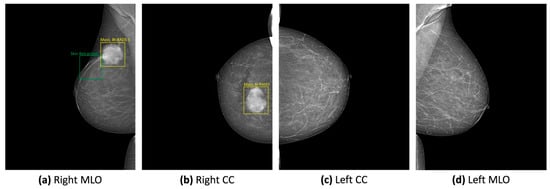

Mammograms are X-ray images used for breast screening, typically involving two or more images per breast taken from craniocaudal (CC) and mediolateral oblique (MLO) angles. They help identify masses, calcifications, and other abnormalities, with calcifications categorized as either macrocalcifications, which are generally harmless, or microcalcifications, which can indicate early-stage cancer if clustered [11].

To be considered significant, masses in breast tissue must be visible in at least two imaging views, as shown in Figure 1. These masses can appear in various shapes and sizes, with clear boundaries visible on mammograms. Generally, masses that look abnormal have a higher likelihood of being dangerous. Calcifications scattered throughout the breast are typically benign. However, those that are concentrated in a specific region (diffused across the breast but not within the ducts) are usually non-invasive. In contrast, segmental (within ducts), linear (aligned within a duct), or clustered calcifications (more than five within 1–2 cm of tissue) are strong indicators of malignant (invasive) findings [12].

The VinDr-Mammo dataset is designed for classifying and detecting breast cancer in mammograms, using rectangular coordinates to annotate lesions, as seen in Figure 4, which limits its use for image segmentation. It categorizes findings into mass, calcification, asymmetry, and distortion, incorporating BI-RADS evaluations and standardized breast tissue density assessments. However, a significant limitation is the lack of pathology-confirmed results, making the findings dependent on radiology experts. Additionally, the dataset primarily focuses on malignant cases, with only lesions classified as BI-RADS greater than 2 being annotated, leaving many benign findings unmarked. Despite these drawbacks, the dataset offers advantages such as public accessibility, accurate BI-RADS evaluations for density and classification, and a well-structured train/test data split that maintains a consistent sample distribution across various attributes, including patient age [21].